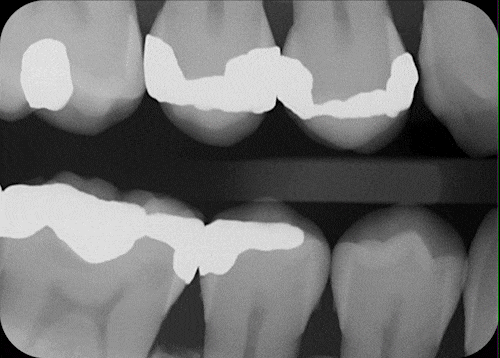

The dental patient journey has always begun in the dimly lit fog of a grayscale radiograph. Until now. When practices turn on the power of AI, x-rays burst with brilliance, offering a technicolor roadmap to dental health.

Viewed under the bright lights of AI, x-rays show up with more clarity and focus, offering dentists a stronger diagnostic foundation for their treatment recommendations and giving patients real confidence that the treatment is necessary.